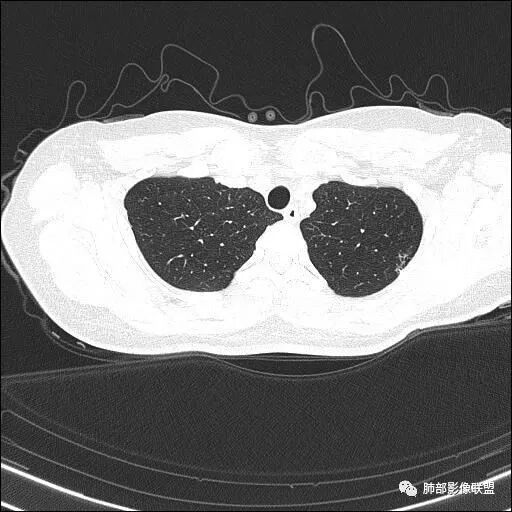

好像其他区域肺气肿不明显啊

觉得还是以网格为主,就是间质为主的特点

我考虑肺气肿,是觉得内部纹理都在

只是稍膨隆,密度稍低高密度灶符合网状为主,所以朝肺气肿考虑

张延军:青年间隔旁型的不少见